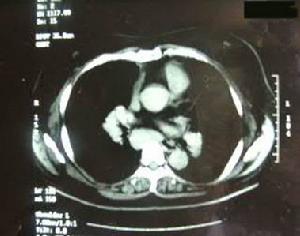

2.腦血管造影大多正常,僅偶爾有血管炎健的表現腦CT常表現有病變區密度勱的輕度增高,經造影劑強化後病變呈均一強化,周圍可出現水腫帶。MRI對神經系統結節病的診斷具有較高敏感性可顯示腦室周圍白質有T2加權的高信號變化T1加權像呈多種信號混雜有腦膜病變時,強化掃描可發現腦膜強化。3.放射性核素67鎵(67Ga)掃描對結節病診斷價值較高可早期發現肺部病灶有學者認為67Ga掃描與血清血管緊張素Ⅰ轉換酶兩者的結合對結節病的診斷準確率為80%~90%。4.腦膜和腦組織或周圍神經的活檢可明確診斷。